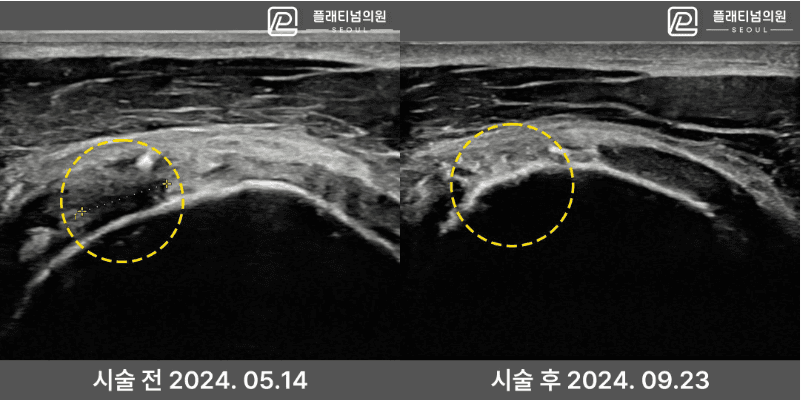

인대재생주사 시술 전후 초음파

실제 환자의 시술 전후 초음파 비교입니다. 파열되어 결손이 있던 인대 조직이 시술 후 회복된 것을 확인할 수 있습니다.

4세대 인대재생주사 시술 후 초음파 확인 결과

인대 조직 재생 확인 — 시술 전후 비교

* 개인차가 있을 수 있으며, 모든 환자에서 동일한 결과를 보장하지 않습니다.